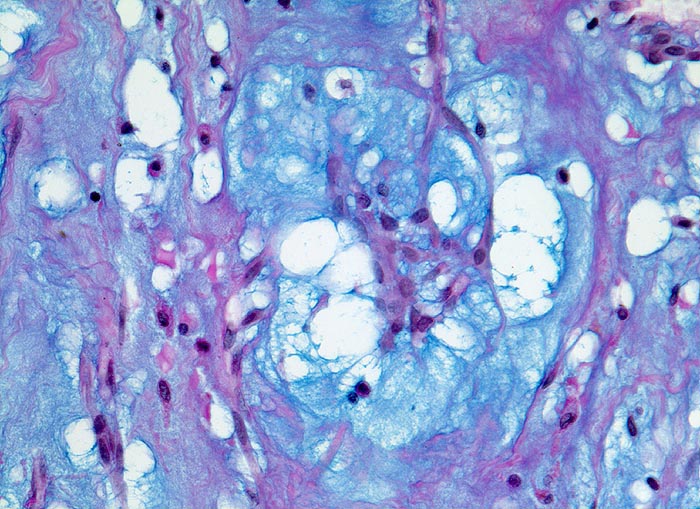

PathoPic ID 3008 - Vorhofmyxom

Vorhofmyxom

benigner Tumor

Herz Vorhof

Kardiovaskuläres System

Eine kleine Gruppe von spindelförmigen Tumorzellen liegt eingebettet in ein myxoides Stroma mit locker eingestreuten Entzündungszellen.

Histologie

320